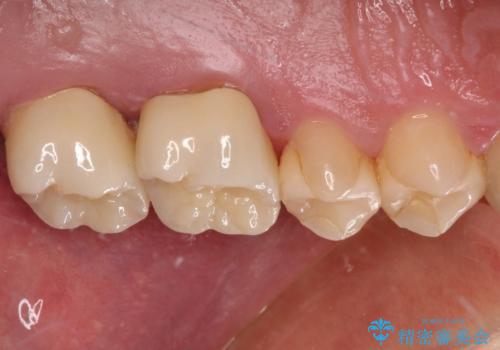

根管治療後、病変が消退したことを確認し、オールセラミッククラウンにて補綴治療を行うこととしました。

2,3回の処置後には来院時に感じていた痛みはなくなり、根管治療から半年後にはレントゲンでの根尖部病変も消失していました。

はじめに処置をしていた医院に通っていたら、2本とも抜歯されていたかと思うとゾッとするおっしゃっていました。